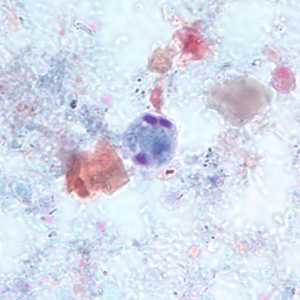

E. gingivalis trophozoites stained with trichrome.

Figure A: Trophozoite of E. gingivalis from culture, stained with trichrome.

Figure B: Trophozoite of E. gingivalis from culture, stained with trichrome.

Figure C: Trophozoite of E. gingivalis from culture, stained with trichrome.

Figure D: Trophozoite of E. gingivalis from culture, stained with trichrome.